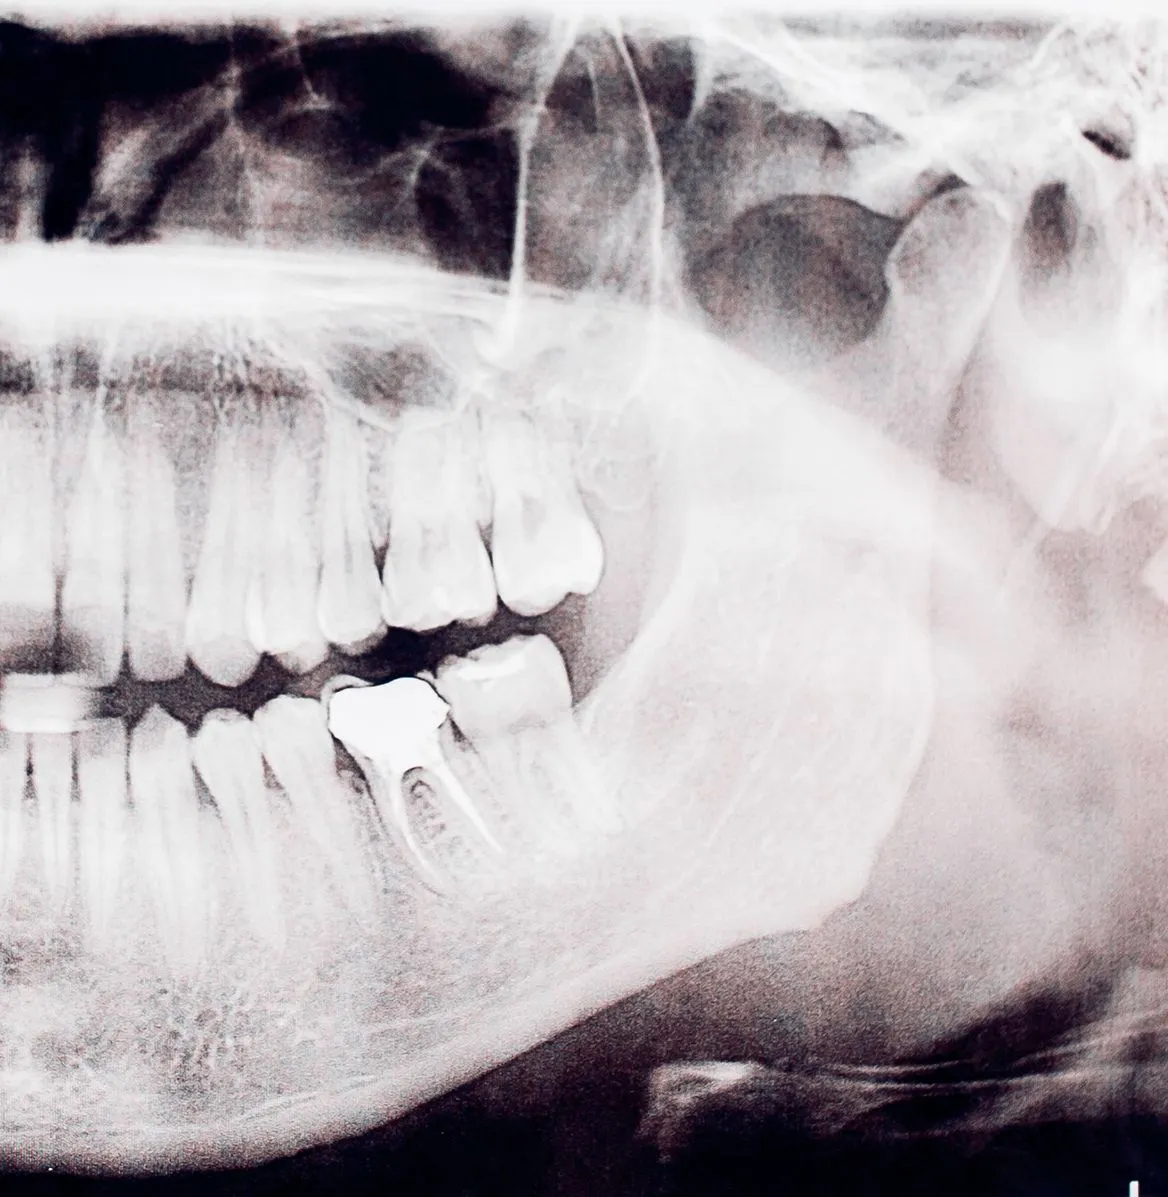

Inside each tooth is a soft tissue called the pulp, which contains nerves and blood vessels. If this becomes infected or inflamed due to decay, trauma, or a deep filling, it can cause severe pain or lead to an abscess.

- Removing the infected or damaged pulp

- Cleaning and disinfecting the inside of the tooth

- Filling and sealing the space to prevent future infection

5. Filling the Root – The root canals are filled and sealed with a material called gutta-percha.